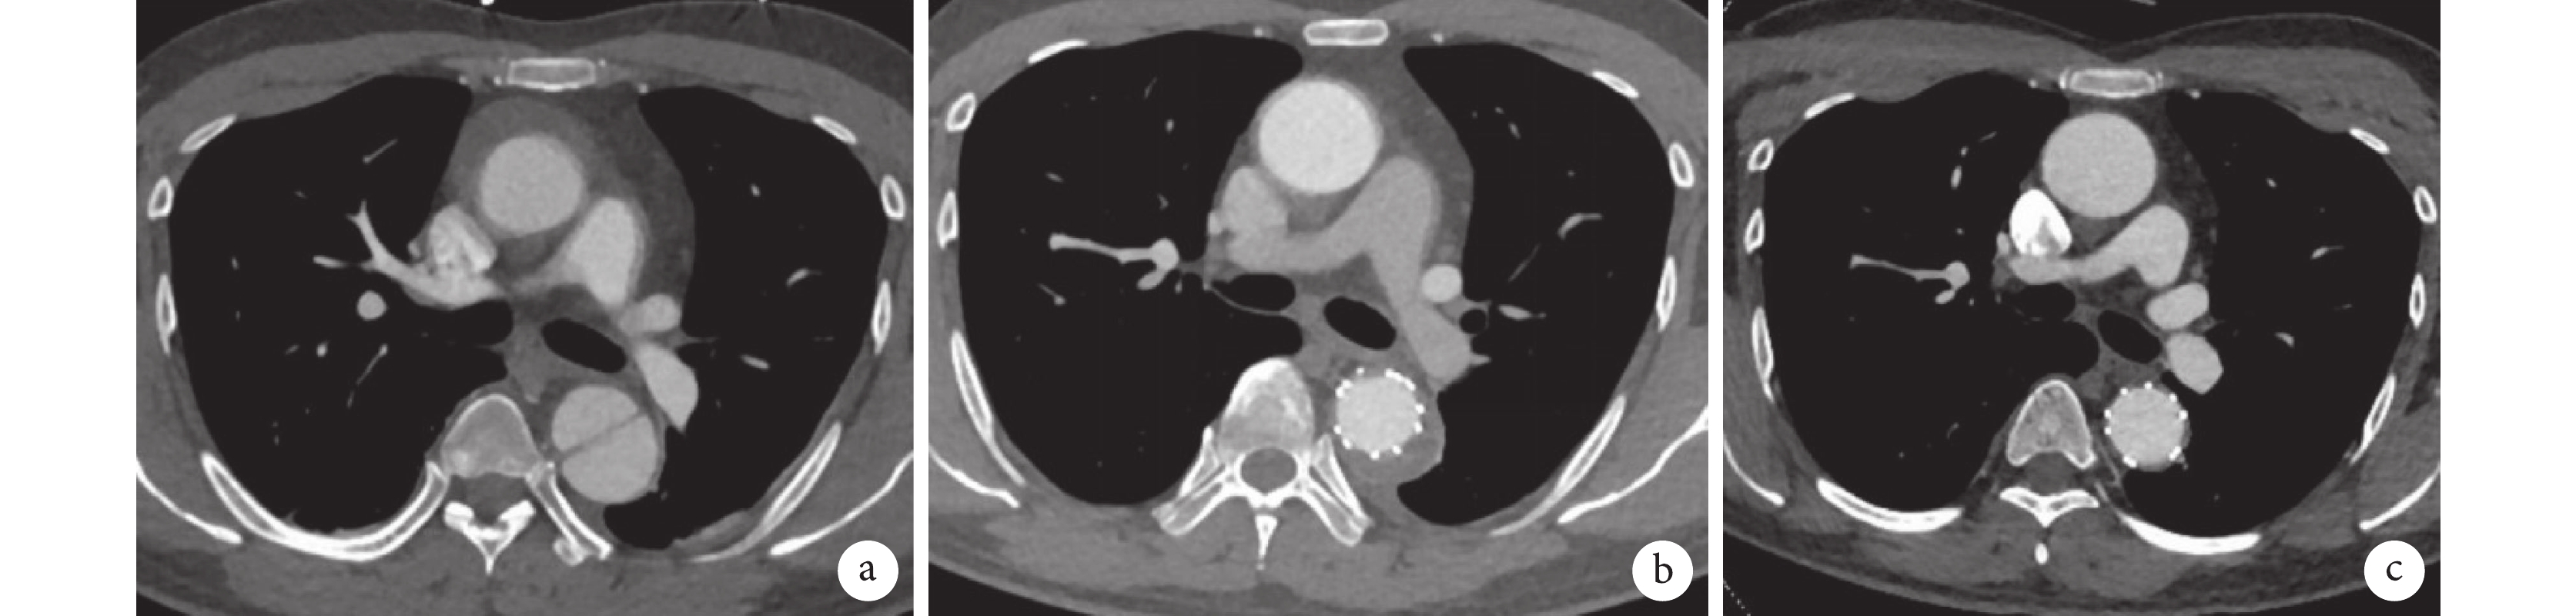

平均隨訪5~28(21±7)個月。隨訪期間未發現截癱、神經系統并發癥、腎衰竭、左上肢缺血、夾層破裂等并發癥。復查CTA提示支架形態良好,無支架移位及內漏發生。所有患者IMH完全或幾乎完全吸收,降主動脈假腔或血腫縮小(圖3)。1例患者(9)支架近端新發破口,并在TEVAR術后1周接受開放手術。截至最后一次隨訪主動脈CTA,所有患者升主動脈血腫、降主動脈血腫或假腔厚度均顯著降低(表3、圖4)。No.9患者術前CTA提示主動脈弓部未見明確破口或潰瘍,行單分支支架置入,術中支架通暢,未見內漏,術后患者持續胸痛不緩解,術后1周復查主動脈CTA提示小彎側支架近端新發破口,再次行開胸手術置換升主動脈及部分主動脈弓(圖5),術后患者恢復情況良好。此并發癥出現可能有以下原因:(1)該患者入院時因存在血壓下降,胸腔積液,存在持續性胸痛不緩解,擔心血管有破裂風險,在發病第1 d即接受了急診支架型腔內修復術(TEVAR)手術治療,患者急性期手術,血腫內膜可能不穩定,易破裂有關。(2)患者有夾層家族史,父親因夾層去世,不排除有血管壁先天性質量問題。(3)患者LSA近端直徑測量27 mm,因急診手術缺貨,術中不得已選取了較大型號支架(32 mm),oversize過大導致內膜撕裂。

a:提升升主動脈血腫,降主動脈夾層改變;b:術后1個月復查主動脈CTA提示升主動脈血腫完全吸收,降主動脈真腔擴張,假腔血栓化縮小;c:術后6個月復查主動脈CTA提示升主動脈,降主動脈血腫完全吸收